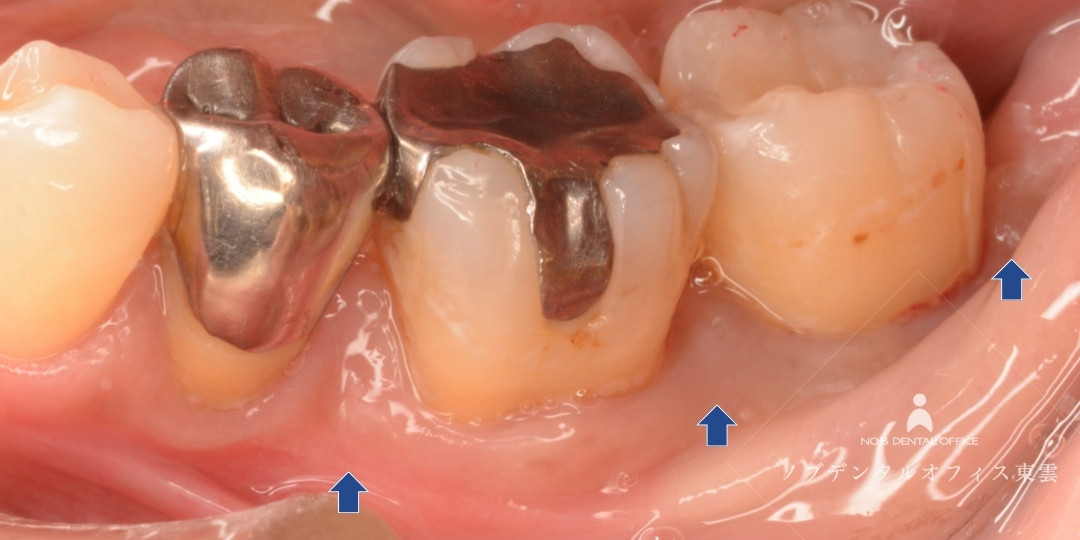

歯周基本治療をした後の写真。歯ぐきが引き締まりました。

リグロスを用いた歯周組織再生療法後、骨の再生が認められました。※写真内赤線箇所

診断の結果、レントゲンが黒くなっている部分があり、骨が吸収されていました。中等度の歯周病です。

歯周基本治療を行い、歯周組織再生療法を行いました。